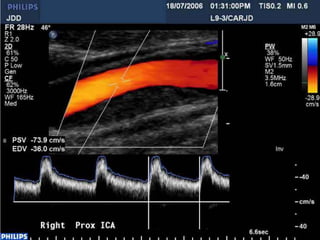

Monitoring fetal growth and well

being

 Doppler investigations